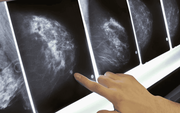

• Cô gái 28 tuổi mắc ung thư vú sau 1 năm chạy bộ buổi sáng, bác sĩ cảnh báo: Có 3 thói quen này thà đừng chạy còn hơn

Cô gái 28 tuổi mắc ung thư vú sau 1 năm chạy bộ buổi sáng, bác sĩ cảnh báo: Có 3 thói quen này thà đừng chạy còn hơn